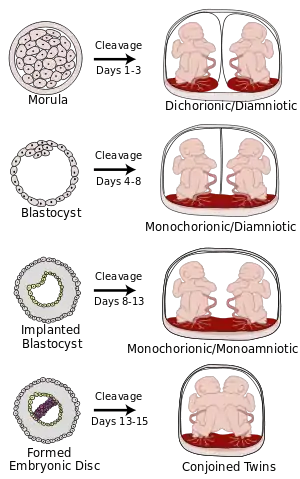

تعتمد درجة انفصال التوائم في الرحم على إذا ما تم الانقسام إلى بويضتين مخصبتين ووقت الانفصال. دائما ما تنتج التوائم ثنائية الزيجوت من بويضتين مخصبتين. بينما تنقسم التوائم أحادية الزيجوت إلى بويضتين مخصبتين في وقت ما مبكر جدا من الحمل. ويحدد توقيت هذا الفصل المشيمية (عدد المشيمة) وعدد الأكياس السلوية للحمل. التوائم ثنائية المشيمة إما أنها لم تنقسم أبدا (كانت بويضتين ملقحتين) أو أنها انقسمت في غضون الأربعة أيام الأولى. بينما تنقسم التوائم أحادية الكيس السلوي بعد الأسبوع الأول.

في حالات نادرة جدا، تصبح التوائم ملتصقة. تتشكل التوائم الزيجوتية غير الملتصقة حتى اليوم الرابع عشر من التطور الجنيني، ولكن عندما تحدث التوأمة بعد 14 يوما، من المرجح أن تكون التوائم ملتصقة.[39] وعلاوة على ذلك، يمكن أن تكون هناك اختلافات في البيئة المشتركة للتوائم في الرحم، مما يؤدي إلى مضاعفات الحمل.

ومن المفاهيم الخاطئة الشائعة أن وجود مشيمتين يعني أن التوائم ثنائية الزيجوت. ولكن إذا انفصلت التوائم أحادية الزيجوت في وقت مبكر بما فيه الكفاية، يصبح ترتيب أكياس السلى والمشيمة في الرحم لا يمكن تمييزه عن التوائم ثنائية الزيجوت.

| النوع | الوصف | اليوم |

| ثنائي المشيمة-ثنائي الكيس السلوي | عادة، تسمى التوائم التي لها مشيمتان وكيسان سلويان منفصلان ثنائية المشيمة ثنائية الكيس السلوي. ويحدث ذلك في جميع حالات التوائم ثنائية الزيجوت تقريبا (باستثناء حالات نادرة جدا من اتحاد الكيسة الأريمية لهما[40]) وفي 18-36٪[41] (أو حوالي 25٪[40]) من التوائم أحادية الزيجوت (المتطابقة).

التوائم ثنائية المشيمة ثنائية الكيس السلوي لديها أدنى معدلات لخطر الوفيات يصل إلى حوالي 9%، على الرغم من أن ذلك لا يزال أعلى بكثير من الولادات المفردة.[42] |

تتشكل التوائم ثنائية المشيمة ثنائية الكيس السلوي عندما يحدث الانقسام في اليوم الثالث بعد الإخصاب.[40] |

| توائم أحادية المشيمة ثنائية الكيس السلوي | توائم أحادية المشيمة تشترك في المشيمة نفسها.

عادة تسمى التوائم أحادية المشيمة التي لها كيسان سلويان (أحادية المشيمة ثنائية الكيس السلوي)، والتي تحدث في 60-70٪ من حالات الحمل مع التوائم أحادية الزيجوت،[41] وفي 0.3٪ من جميع حالات الحمل.[43] التوائم أحادية المشيمة - ثنائية الكيس السلوي تكون دائما تقريبا أحادية الزيجوت، مع بعض الاستثناءات التي تتحد فيها الكيسة الأريمية.[40] تشترك التوائم أحادية المشيمة في المشيمة نفسها، وبالتالي هناك خطر حدوث متلازمة نقل الدم الجنيني. |

اليوم الرابع إلى الثامن |

| أحادي المشيمة أحادي الكيس السلوي | تشترك التوائم أحادية المشيمة في نفس الكيس السلوي في 1-2٪ من حمل التوائم أحادية الزيجوت.[41]

عادة ما تكون التوائم أحادية الكيس السلوي أحادية الزيجوت.[44] معدل البقاء على قيد الحياة للتوائم أحادية الكيس السلوي بين 50٪[44] إلى 60٪.[45] التوائم أحادية الكيس السلوي، كما هو الحال مع التوائم ثنائية الكيس السلوي أحادية المشيمة، لديهم خطر حدوث متلازمة نقل الدم الجنيني. أيضا، تزداد فرص التفاف الحبلين السريين حول الأطفال. وبسبب ذلك، تتزايد فرص إجهاض حديثى الولادة أو المعاناة من الشلل الدماغي بسبب نقص الأكسجين. |

تحدث التوائم أحادية الكيس السلوي عندما يحدث الانقسام بعد اليوم التاسع من الإخصاب.[40] |

| التوائم الملتصقة |

عندما ينقسم الزيجوت المتطور إلى جنينين، يحدث ذلك في 99٪ من الحالات في غضون 8 أيام من الإخصاب. الوفيات هي الأعلى بالنسبة للتوائم الملتصقة بسبب العديد من المضاعفات الناتجة عن الأعضاء المشتركة. |

إذا انقسم الزيجوت بعد اليوم الثاني عشر، عادة ما ينتج توأم ملتصق. |